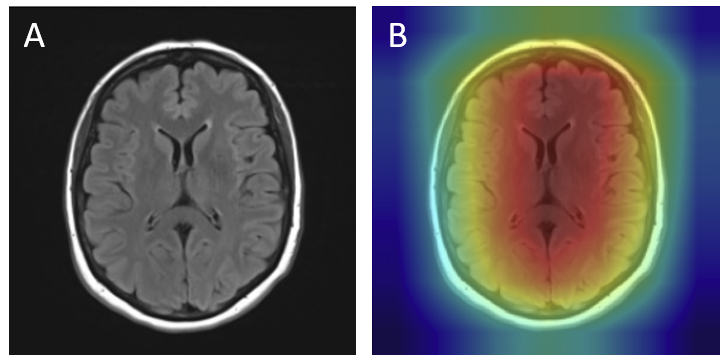

Grad-CAM visualizations of correctly classified cases confirm that the model focuses on regions consistent with radiological expectations. In these overlays, warmer colors (red and orange) highlight the areas where the network places the greatest emphasis during prediction, while cooler colors (blue) correspond to regions with minimal contribution. This distinction allows direct inspection of whether the model bases its decision on clinically relevant cues.

For gliomas, the heatmaps align with intra-axial lesions exhibiting infiltrative margins (Figure 8). Meningiomas are accurately identified at dural or peripheral attachment sites, consistent with their extra-axial presentation (Figure 9). Pituitary adenomas are localized to the sella turcica with concentrated red activation at the lesion boundaries (Figure 10). Finally, in no tumor cases, the activation maps remain diffuse or midline-focused without strong hotspots, consistent with normal anatomy (Figure 11). The correspondence between the model's attention and radiological landmarks indicates that the network is learning meaningful diagnostic features rather than relying on spurious correlations.

Figure 11: No tumor — original (A) vs. Grad-CAM (B), correct model prediction.

No Tumor Correct